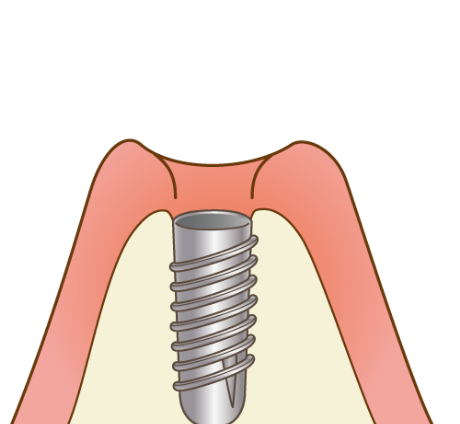

当院のインプラントは、40年以上の歴史があるノーベルバイオケア社(スイス)を使用しており、骨との親和性に優れる「純チタン」の表面に「タイユナイト」と呼ばれる表面加工が施されており、周囲の骨形成が促進されると言われています。